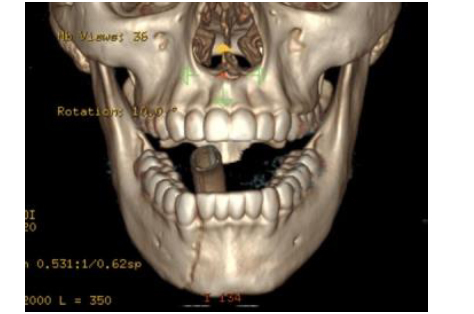

A 32-year-old man undergoes open reduction and internal fixation of a fracture in the left body of the mandible. A six-hole dynamic compression plate is chosen for the inferior mandibular border. The first screw is placed bicortically through a plate hole immediately adjacent to the line of fracture. To obtain maximum compression at the fracture line using the spherical gliding principle, the most appropriate next step is to drill for a second screw at which of the following locations (A–E)?

The correct response is Option A.

To obtain maximum compression at the fracture line using the spherical gliding principle, the most appropriate next step is to drill for a second screw eccentrically, away from the line of fracture, through a plate hole located across the fracture line.

Concentric or neutral drilling occurs in the center of a plate hole, while eccentric drilling occurs in the periphery (corner) of the plate hole (either away or closer to the line of fracture).

The figure above illustrates the spherical gliding principle in a dynamic compression plate. The special geometry of the plate hole—together with eccentric, away from the fracture line, placement of the screw that has a spherically shaped head—allows interfragmentary compression in an axial direction when the screw is driven fully into the plate hole. For appropriate fracture compression to occur, the head of the screw that was placed first must be well seated into the plate hole, stabilizing the plate against the underlying bony segment.

Drilling concentrically (neutrally) through a plate hole located across the fracture line would cause no axial movement of the underlying bone fragments upon tightening of the screw against the plate, generating no further compression at the fracture line.

Drilling eccentrically, closer to the line of fracture, through a plate hole located across the fracture line would increase the fracture gap upon tightening of the screw against the plate.

Placement of a second screw in a plate hole located on the same side of the first screw (in relation to the line of fracture) would have no effect over the fracture line. Also, after eccentric (away from the line of fracture) placement of one screw on each side of the fracture, the remaining screws should be placed concentrically.